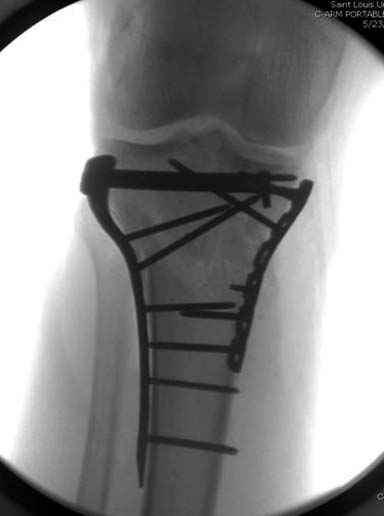

Скажите пожалуйста что навело на такой синтез? Выбрали не самый лучший способ фиксации-штифт и пластина? 2 противоположных методики.

Такой выбор обусловлен "плохим" состоянием мягких тканей в нижней трети голени. К тому же пациент гиперстеник и открытая методика нами сочлась не совсем удобной.

Уважаемый коллега! а зачем ДВЕ конструкции? У Вас железо бесплатное? Вполне можно было бы обойтись чем то одним.

Чем одним??? Использование штифта не решит проблемы - перелом затрагивает мыщелки и проходит еще на уровне бугристости. Использование пластины на длинной ножке даже при подкожном введении предполагает высокую травматичность на фоне сохраняющегося отека. А так - 3 см разрез для штифта и 10 - для пластины.

Способ фиксации сам по себе - вполне приемлемый. Однако фиксации должна предшествовать репозиция.

Боюсь, задача восстановления формы суставной поверхности tibia осталась нерешенной.

Имелась центральная компрессия. Проводилась артротомия - суставная линия полностью восстановлена. Произведу контрольные рентгенограммы для доказательства.

Владимир! С Ваших слов ткани"плохие" в нижней трети, а перелом намного "выше", тем более блокировать штифт в нижней трети.И по поводу травматичности -у Вас получилось поболее ее. В принципе Вы достигли результата-"собрали перелом". Я бы сделал-1 опорной пластиной. Если была импрессия плата чем замещали дефект? Просто на снимке не видно.

Про противоположность методик(штифт+пластина) - неординарный перелом. поэтому решили скомбинировать. Получилось вполне стабильно.

Имеющаяся импрессия не потребовала пластики - достаточным оказалось поднять отломок.

Для адекватной оценки необходимо предоставить хотя бы по две проекции до и после синтеза. Снимки после синтеза - с захватом всей длины сегмента т.к. использовался гвоздь. По предоставленной одной некачественной проекции сказать можно только сказать что и решение, и результат спорные.

Решили выполнить остеосинтез штифтом и внутрисуставного перелома пластиной и винтами. Жду мнения! Зачем мне оправдываться-я же не преступник. Диалогом называется...

Отдельные переломы тибиал плато и перелом проксимальной трети большеберцовой кости отличаются от переломов тибиал плато с вовлечением диафиза. Здесь перелом тибиал плато типа Schatzker VI, полученный в результате высокоэнергетической травмы. Перелом метафиза образовал отрыв суставной поверхности от диафиза с вовлечением медиального и латерального мыщелков. Двухмыщелковые переломы из-за укрочения опасны развитием компартаментального синдрома, повреждением латерального мениска и связок.

Одна из проблем фиксации тибиал плато - это предупреждение мягкотканых осложнений, и это достигается проведением поэтапной фиксации. Такая тактика - первым этапом дистракция любым наружным фиксатором, а затем по готовности кожных покровов и после спадения отека операция. Операция в ранние сроки и без адекватной готовности кожных покровов лимитирует ваши действия опасностью осложнении, но без адекватного доступа фиксация получается ущербная. Для предупреждения осложнений лучше подождать и в зависимости от серьезности травмы можно ожидать иногда от 1 до 2 недель.

При переломах одного из мыщелков тибиал плато+дополнительный перелом проксимальной трети большеберцовой кости можно применить комбинированный вариант фиксации, т.е. мыщелок винтами или пластиной, а для диафиза можно установить гвоздь. В данном варианте потеряно преимущество гвоздя , из-за серьезной травмы суставной поверхности нельзя нагружать ногу несколько месяцев. А без нагрузки гвоздь просто заполнитель пространства внутри кости!

На вашем место я бы подождал с фиксацией до готовности кожных покровов, и за это время можно было подобрать соответствующий фиксатор, т.е более длинная пластина снаружи и медиальная пластина на апексе перелома как подпорка. Здесь приемлем как раз минимальный доступ.

Имеющаяся импрессия не потребовала пластики - достаточным оказалось поднять отломок

Если там действительная импрессия, пустое место без структуральных заполнителей, кость или синтетические материалы, не восстановится, а образуется коллапс, и ось конечности поведет после нагрузки. Кроме того там возможно "болт стяжка"?, в медиальной стороне выступает за кортекс, можно было укоротить! Потом создается впечатление, что не соответствуют мыщелки большеберцовой и бедренной костей? Покажите снимок.